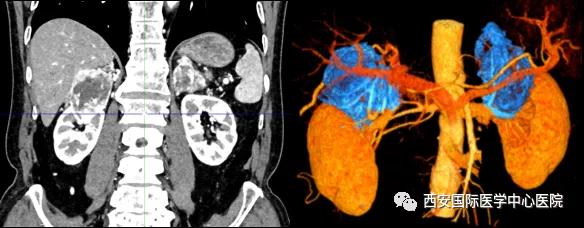

今年七十五歲的患者,來自陜西省商洛市,四月前因腰背部疼痛就診于當?shù)蒯t(yī)院,行CT檢查發(fā)現(xiàn)“右腎、雙側(cè)腎上腺占位,前縱膈淋巴結腫大,雙肺多發(fā)結節(jié)、胸椎骨質(zhì)破壞,考慮轉(zhuǎn)移瘤”。為進一步診斷治療,患者的兒子帶他來到西安某三甲醫(yī)院,查泌尿系CT提示“右腎占位性病變,多考慮腎癌,雙側(cè)腎上腺多發(fā)轉(zhuǎn)移灶,腹膜后多發(fā)腫大淋巴結”;行穿刺活檢提示“腎透明細胞癌”;并給予患者口服靶向藥物的治療方案。

自四月份至今,患者一直口服靶向藥物治療(阿昔替尼5mg 2次/日),期間無不良反應,目前腰背部疼痛癥狀也有所緩解,復查影像學資料提示瘤體較前縮小,腫瘤完整切除的可能性明顯提高;而且患者的兒子也是一名外科醫(yī)生,所以他更想為父親完成后續(xù)的手術治療。

患者一家慕名前來到西安國際醫(yī)學中心醫(yī)院找到楊增悅教授。楊增悅教授仔細看完患者的之前的影像學及病理資料后,診斷為:右腎透明細胞癌(T4N1M1);并安排他住院。而后,主管醫(yī)生及時為他完善了術前檢查及評估。7月15日,在麻醉手術中心柴偉主任、王彬榮副主任、李娟護士長、李瑞剛護士長及全體麻醉手術中心團隊的有力保障下,成功完成了這臺“大”手術。